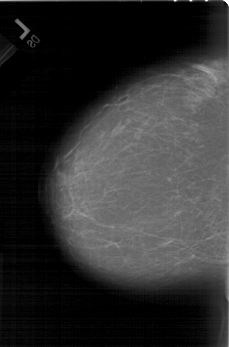

A_1440_1.RIGHT_MLO

RIGHT_MLO LINES 6871 PIXELS_PER_LINE 4501 BITS_PER_PIXEL 12 RESOLUTION 43.5 OVERLAY